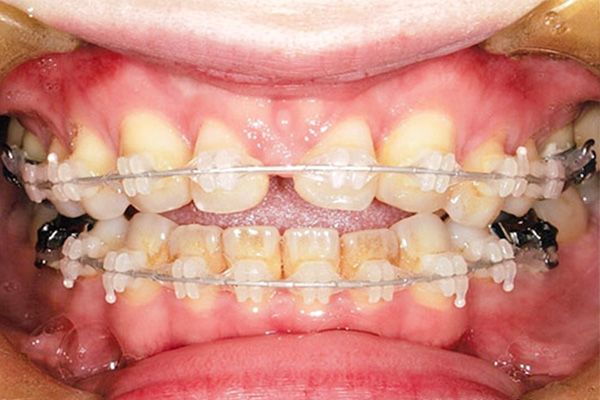

治療前